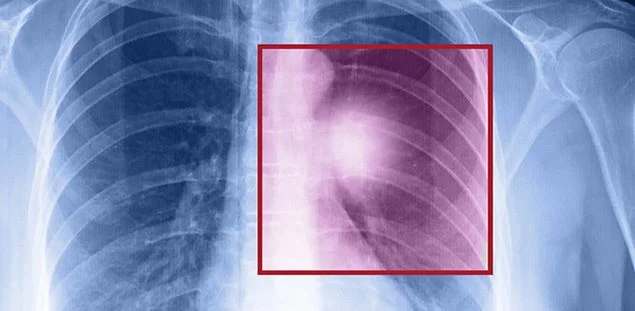

Sağlık Bakanlığı Kanser Daire Başkanlığı’nın verilerine göre, Türkiye’de her yıl yaklaşık 30 bin kişiye akciğer kanseri tanısı koyuluyor. Sigara tek başına akciğer kanserleri nedeniyle ölümlerin 87’sinden sorumlu tutuluyor. Oldukça ölümcül bir kanser türü olan akciğer kanseri tedavisinde son yıllarda yaşanan olumlu gelişmeler hastaların umudunu giderek daha fazla arttırıyor. Ancak uzmanlar uyarıyor; tedavi seçenekleri artsa bile akciğer kanserinden korunmanın en iyi yolu sigaradan uzak durmak. 17 Kasım Dünya Akciğer Kanseri Günü nedeniyle açıklamalarda bulunan Akademik Onkoloji Derneği Başkanı Prof. Dr. Erdem Göker, ailesinde akciğer kanseri veya sigara içenlerin bu kanser türü için ciddi bir risk altında olduklarını hatırlattı.Resmi verilere göre, erkeklerde en sık, kadınlarda ise beşinci sıklıkta görülen ve her yıl yaklaşık 30 bin yeni tanı konulduğu tahmin edilen akciğer kanseri erkeklerde tüm kanserlerin yüzde 21,8’ini, kadınlarda ise yüzde 4,9’unu oluşturuyor. Sigaranın tek başına kanserden ölümlerin %30’undan, akciğer kanserleri nedeniyle ölümlerin ise %87’sinden sorumlu olduğunu vurgulayan, Prof. Dr. Göker “Akıllı tedaviler, hedefe yönelik tedaviler ve immünoterapi kanser hastalarına umut veriyor” dedi.

Akciğer kanserinin tüm kanserler içinde en çok görülen ve aynı zamanda da en çok öldüren kanser çeşidi olduğunu söyleyen Prof. Dr. Erdem Göker, “Akciğer kanserinin pek çok kanser çeşidi vardır ancak en yaygın görülen iki türden biri yassı hücreli akciğer kanseri, diğeri ise adeno kanserdir. Bu iki kanser, küçük hücreli olmayan akciğer kanseri diye tanımladığımız gruba dahil. Bir de küçük hücreli akciğer kanseri dediğimiz grup var ancak bu tür, tüm akciğer kanserlerinin %20’sinden azında görülüyor. Yani akciğer kanseri vakalarının %80’i küçük hücreli olmayan akciğer kanseri diyebiliriz” dedi.